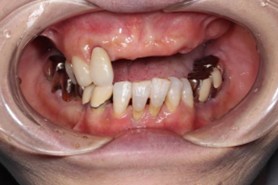

50代 男性

治療前

治療後

治療後- 年齢/性別

- 50代/男性

- 主訴

- 上顎の義歯の具合が悪いため、インプラント希望

- 治療期間

- 1年間

- 治療費

- インプラント¥4,400,000

骨造成¥220,000

サージカルステント¥99,000 - リスク・副作用

- 術後の腫れ・出血